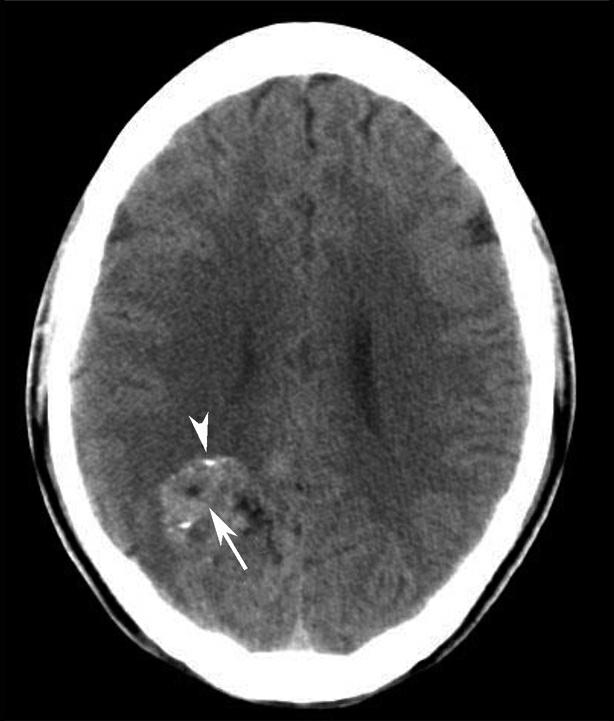

破裂孔、卵圆孔、棘孔及斜坡等均为重要的解剖结构,临床常见疾病如鼻咽癌常侵犯上述结构(图1-2-3)。颈静脉孔区较常见的肿瘤为颈静脉球瘤,常伴有颈静脉孔及其邻近骨质的破坏(图1-2-4)。

图1-2-3 鼻咽癌颅底骨质破坏

A.横断面;B.横断面(骨窗)

骨窗示左侧岩尖、斜坡、左侧蝶骨大翼骨质破坏、受侵(白箭),肿瘤经破裂孔侵入颅内(黑箭头)